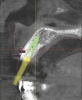

With all of this needed information relative to the pre-operative condition and proposed final tooth position, the treatment moved into the assessment and planning phase. The CBCT revealed an intact buccal plate anterior to the root of tooth No. 8 with adequate bone surrounding the area in all dimensions. Because of the favorable bony contours, an immediately placed implant was decided upon and planned in the software. The CEJ of the proposed final tooth location was identified and an OsseoSpeed EV 4.2 C - 11 mm implant (Dentsply Implants) was planned 3 mm apical and 2 mm lingual to that landmark12 to assure adequate biologic and prosthetic space for the final restoration (Figure 3 through Figure 5). A Simplant SAFE Guide was selected and ordered to convey all of the positional parameters of the final implant position, including depth control and implant timing.

Fig 3 through Fig 5. The Simplant plan of the future implant position 3 mm apical and 2 mm

lingual to the CEJ of the proposed final restoration, including final guide design.